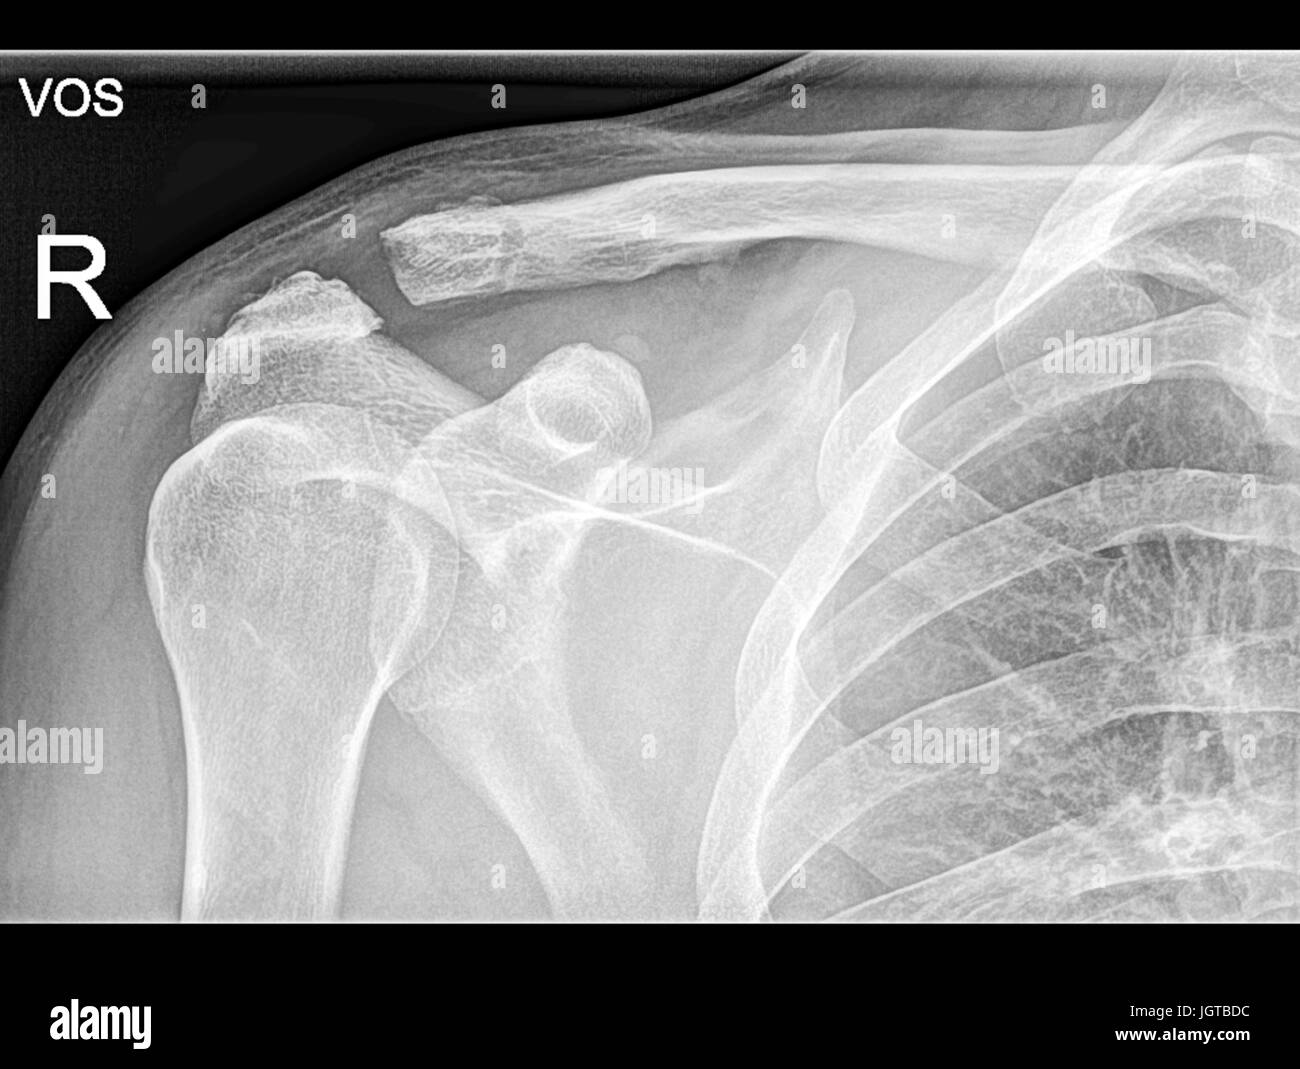

From www.alamy.com

Broken clavicle bone, Shoulder Medical Xray, Patient treatment Stock Clavicle Nailing Procedure  Intramedullary nailing of the clavicle is reserved for young and highly active patients who are expected to resume full active function soon after surgery. The velox tm procedure with sonoma crx® is faster, streamlined, and designed for reproducible, minimally invasive clavicle fracture repair. Nailing approach to the clavicle and many more surgical approaches described step by step with text and. Clavicle Nailing Procedure.